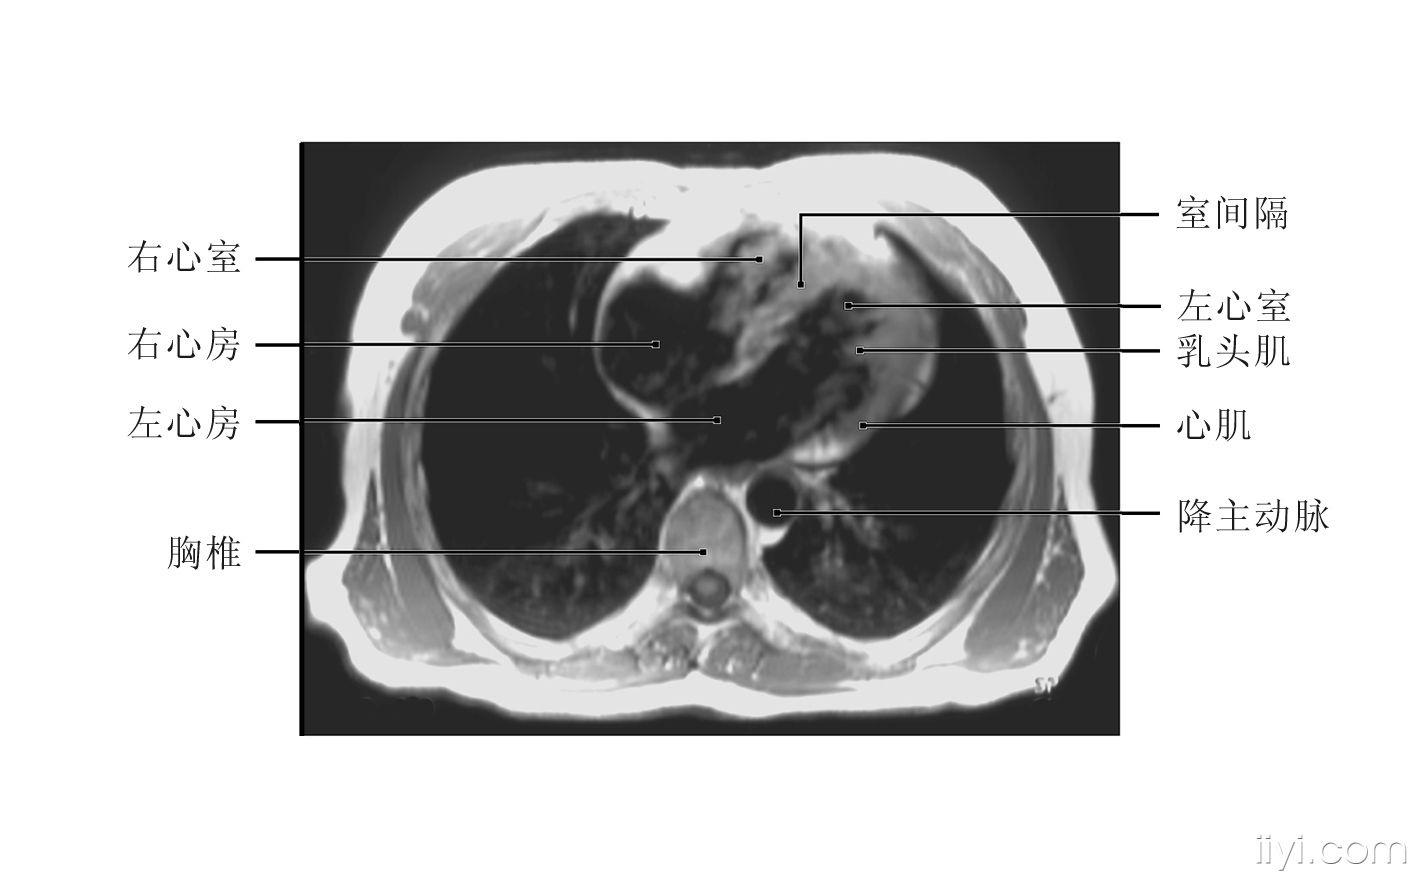

图4-16-心脏横断面正常mri表现.jpg

心脏横切面图片

心脏横切面图片,心脏切面图片